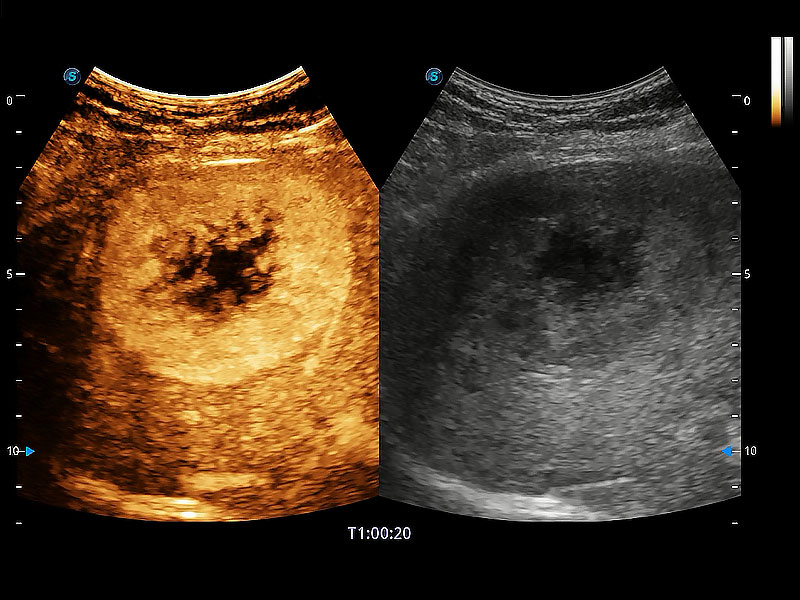

極大提升超低速微細(xì)血流的檢出能力,同時(shí)更精準(zhǔn)地濾除軟組織和超聲信號(hào),為獸用醫(yī)生提供以往無法通過常規(guī)血流獲得的疾病診斷信息。

在傳統(tǒng)二維血流成像的基礎(chǔ)上,呈現(xiàn)血流的立體感,具有動(dòng)感的生命力之美。即便是微小的血管也能輕松應(yīng)對(duì),提高了血流的視覺敏感性。